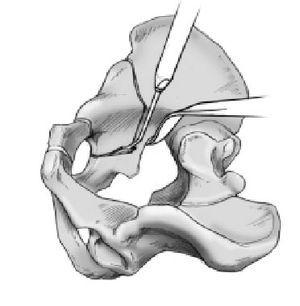

Figura 13 Segundo paso de la segunda osteotomía. Tras terminar el primer corte con sierra se realiza el segundo corte con un escoplo apuntando a la espina ciática. Este osteotomo realiza

un ángulo de 110-120º respecto a la primera sección. Aquí se ha de ir con precaución en no ir demasiado dorsal, ya que puede romperse la columna posterior. De otro modo se tiene que ir bastante dorsal para evitar abrir la parte dorsal de la cadera. En este paso se utilizará un escoplo angulado 30º. La osteotomía se inicia al final de la osteotomía ilíaca y se dirige hacia el separador que se localiza tras la espina ciática. Cuando se sostenga el mango del escoplo absolutamente vertical, se localizará el filo en el plano correcto paralelo a la columna posterior. Esta osteotomía transcurre paralela y aproximadamente 1 cm por delante del límite posterior de la columna dorsal. Al acabar tiene una longitud de unos 4 cm. En todo momento el cirujano debe tener cuidado en mantener la misma distancia al límite posterior de la pelvis.